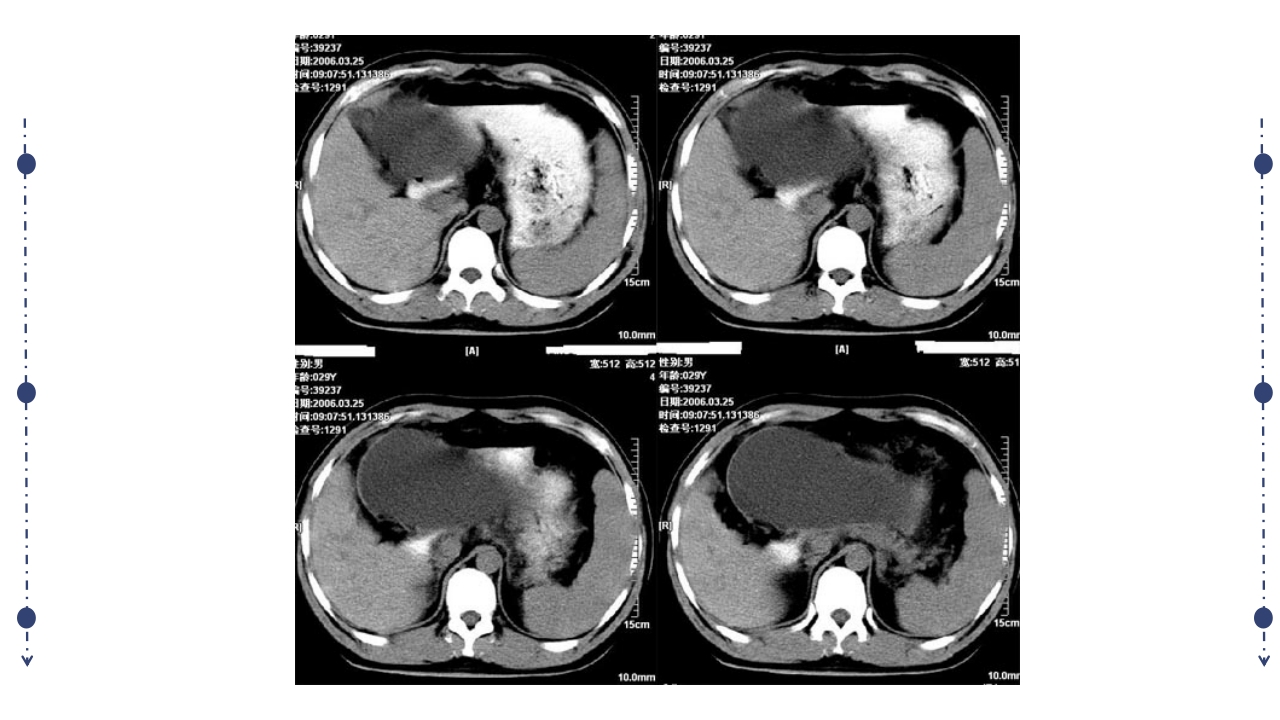

汇报人:xxx 病因 发病机制 病理变化 临床表现,实验室检查,辅助检查 严重程度评估 诊断及鉴别诊断 治疗 急性胰腺炎(AP)定义 急性胰腺炎(acute pancreatitis, AP)是多种病因导致胰酶激活,胰腺组 织自身消化所致的胰腺局部炎症反应(水肿、出血及坏死),病情较重可发 生全身炎症反应综合征(SIRS),并可伴有多脏器功能障碍的疾病。 临床表现以急性上腹痛、恶心、呕吐、发热、血 清胰酶增高等为特点。 常在饱食、脂餐、饮酒后发生。 胰腺的解剖位置 胰管、胆总管共同开口于十二 指肠大乳头肝胰壶腹部 共同通道学说(70-80%) 1. 胆道疾病 2. 酒精 3. 胰管阻塞 4. 十二指肠降部病变 5. 手术与创伤 6. 代谢障碍 7. 药物 8. 感染及全身炎症反应 9....